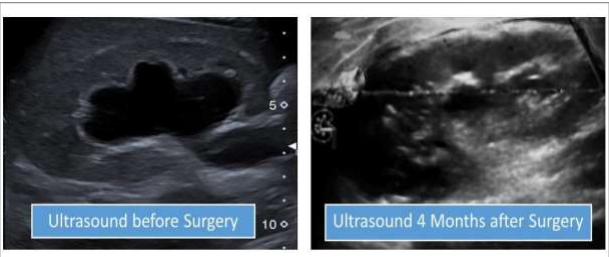

A 15-year-old patient, accompanied by their parents, visited our hospital for the first time. They reported that the child had been experiencing irregular abdominal pain and vomiting several times a week for several years. Despite consulting numerous doctors who suggested allergies and stomach issues as potential causes, the prescribed medications only provided temporary relief. The parents noticed that the pain and daily vomiting episodes had worsened in recent months. Our pediatrician conducted various examinations, including an ultrasound the first the child had ever undergone. The ultrasound revealed a significant dilation of the right kidney's pelvis. I was referred to the case and conducted my own ultrasound examination, ruling out a typical renal pelvis stenosis due to the dilation of the proximal ureter as well.

Patient came to me with his parents 4 months post-surgery for Follow up. He is in very good condition. They informed me that since the operation, the boy has stopped complaining about abdominal pain and vomiting. Now he can eat everything without to think about pain or Nausea. After surgery he has gained 6 kilograms. I performed Ultrasound of right Kidney which showed normal situation with no more Hydronephrosis.